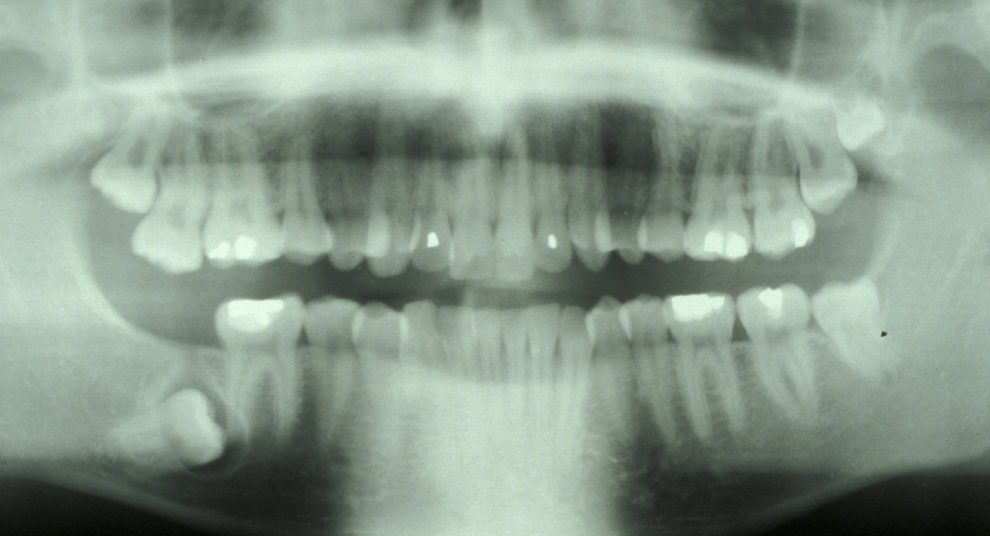

Figure 2 and Figure 3 illustrate examples of indications for removal of a third molar tooth.

Assessment of the tooth is both clinical and radiographic. If somebody presents in pain, it is important to establish that this is coming from the third molar and not elsewhere. Pain is often vague, poorly localised and may be referred from another tooth, or as part of facial arthromyalgia (condition affecting the jaw joint). A dental panoramic radiograph is ideal as it helps to assess all the teeth at once. The health of the adjacent molars may influence the decision whether to remove the third molar or not. Large crowns or old restorations are all at risk of dislodgement during surgery. It is also worth considering whether alternative treatment options are available. For instance, pericoronitis due to an over-erupted upper third molar may be dealt with by extracting that tooth only, with or without operculectomy. In the presence of other teeth of poor prognosis, will it be better in the long term to save the third molar which may be used as a denture or bridge abutment in the future?

These points help to determine whether the tooth can be simply elevated or will need a surgical approach. A series of radiographs depicted in Figure 4 to Figure 8 illustrate these points further.